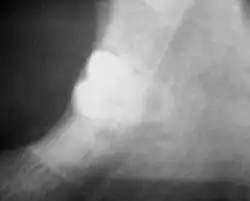

Long-term complications can include periodontal complications such as bone loss on the second molar following wisdom teeth removal. Bone loss as a complication after wisdom teeth removal is uncommon in the young but present in 43% of those of 25 years of age or older.[23] Injury to the inferior alveolar nerve resulting in numbness or partial numbness of the lower lip and chin has reported rates that vary widely from 0.04% to 5%.[23] The largest study is from a survey of 535 oral and maxillofacial surgeons in California, where a rate of 1:2,500 was reported.[26]

Coronectomy

Coronectomy is a procedure where the crown of the impacted wisdom tooth is removed, but the roots are intentionally left in place. It is indicated when there is no disease of the dental pulp or infection around the crown of the tooth, and there is a high risk of inferior alveolar nerve injury.[32]

Coronectomy, while lessening the immediate risk to the inferior alveolar nerve function has its own complication rates and can result in repeated surgeries. Between 2.3% and 38.3% of roots loosen during the procedure and need to be removed and up to 4.9% of cases require reoperation due to persistent pain, root exposure or persistent infection. The roots have also been reported to migrate in 13.2% to 85.9% of cases.[32]